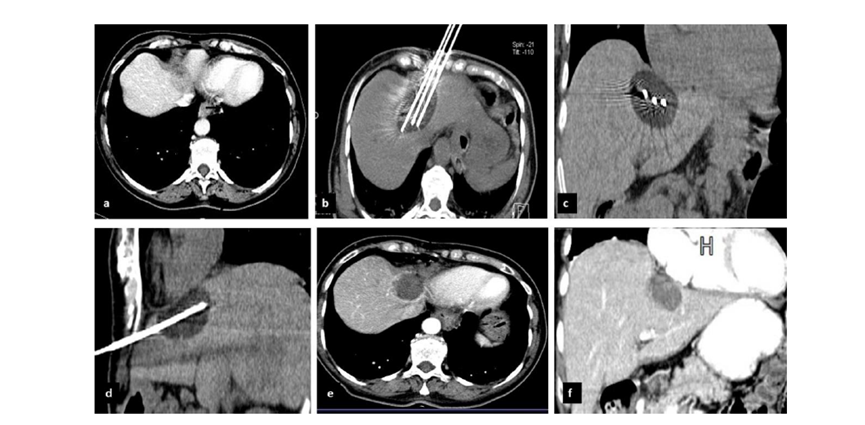

冷凍消融膽囊附近腫瘤病灶

(A)動脈期 MRI 顯示膽囊附近有外周增強病變(箭頭)。

(B)手術過程中 CT 顯示冷凍探針位于病灶內。

(C)消融后,術后 1 個月CT 顯示完全消融(箭頭)。

(A)動脈期CT圖像顯示有一個包膜下結節(jié)(箭頭)。(B)門靜脈期CT圖像顯示病灶區(qū)(箭頭)。(C) 在手術過程中的CT顯示一個冷凍探針位于病灶內。患者在手術及住院期間無并發(fā)癥及重大并發(fā)癥發(fā)生。隨訪時間中位數為7個月(范圍:3-12個月),隨訪期間患者無局部腫瘤進展或死亡。

(A)門靜脈期 CT 圖像顯示膽囊附近有病變(箭頭)。(D)消融手術后 1 個月CT 顯示完全消融。

CT引導的冷凍消融

(c) 19個月后隨訪,沒有發(fā)生局部腫瘤進展。完全消融率為97%(66/68);2名患者均接受了額外的冷凍消融,隨后實現完全消融。平均隨訪期為 12.8 個月(范圍:3-27 個月)。所有患者均接受影像復查(CT 或 MRI)。11個病灶(16.2%)檢測到局部腫瘤進展,6、12和18個月時的累積局部腫瘤進展率分別為4%、8.2%和20.5%。8例出現遠處肝內或肝外病變的患者接受經動脈化療栓塞、經動脈化療栓塞加射頻消融治療或全身化療。